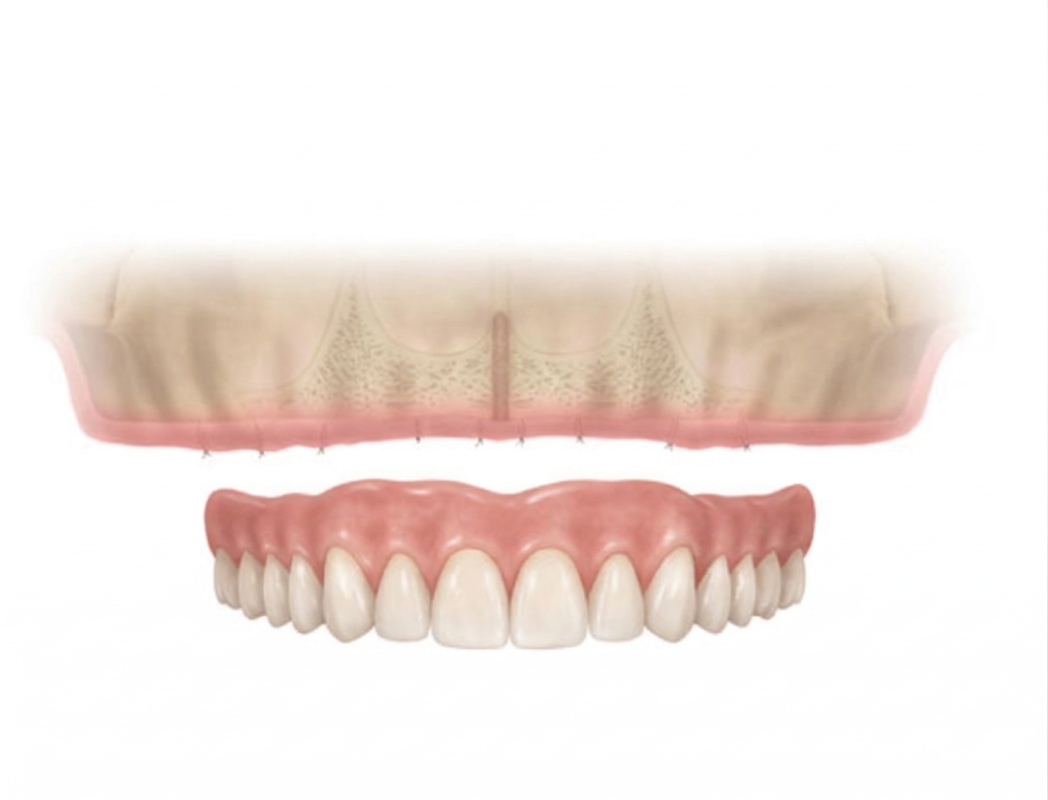

- Removable Implant Overdentures: Removable implant dentures are upgraded from traditional dentures designed to “snap” into place over special attachments using locators, balls, or bars to dental implant posts.

Removable Dentures

4 Implants + Bar + Removable Dentures

Removable implant dentures are economical, easy to clean for long-term use. The treatment is done in 2 phases. Each phase staying for about 10 to 14 days.

The dental implant posts are left to heal for at least 2 to 6 months. During this period, the implant posts fuses with the jaw bone called osseointegration. Certain range of higher range implants have special active surfaces for bone integration to implant. Temporary dentures are worn during the healing period avoiding direct biting pressure over the implant posts as it heals.

3. ATTACHING THE OVERDENTURES

During your return visit, your dentist takes a panoramic x-ray to check if the implant posts is successfully integrated with the jaw bone. Your dentists takes tooth impressions to construct your permanent dentures in the dental labs. On its delivery, locators, balls or bars are screwed into the implant posts with the dentures snapped over securely over.

4. ADJUSTMENTS AND RE-CHECKS

After receiving your final dentures, your dentist makes additional visits to double-check that the dentures fit properly and comfortably. Implant supported dentures provide better retention and comfort.